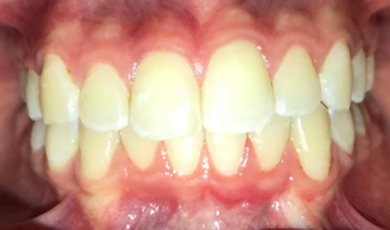

Finalização do tratamento

Após dois anos de acompanhamento o caso foi finalizado, conforme ilustram as imagens abaixo.